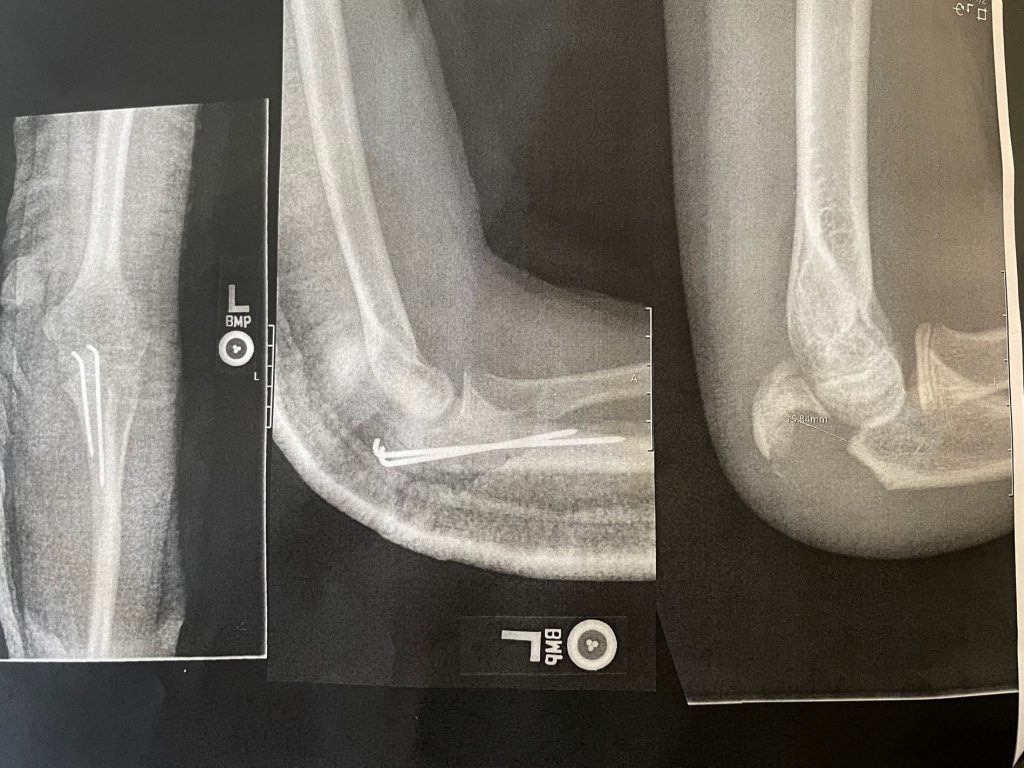

My name is Jayden Cassese and I'm a 12 year old baseball player for the TYA Tigers. In the first pre-season tournament for our big 12U season, I collided with the shortstop sliding into second base and broke off the end of the elbow bone in my left arm. This was the big year for Little League and we had the famous Cooperstown Tournament coming up in July, playing against 100 teams from around the country. I was devastated at the idea of missing that after years of building up to it.

Luckily for us, we knew friends of Dr. Green, and a fellow surgeon at HSS, and both of them strongly recommended we use Dr. Green to repair the elbow. 2 days later I was getting operated on at HSS in Manhattan, and the entire process was handled very well by Dr. Green and his entire staff. After putting 2 pins in my elbow and allowing it several months to heal, while doing PT at HSS along the way, I was able to get back on the field just in time for my big tournament. I came back stronger than ever and hit 2 home runs in one game my first weekend back, then 3 home runs the next week while at Cooperstown! Thank you Dr. Green and team for helping me make it to Cooperstown and beyond.